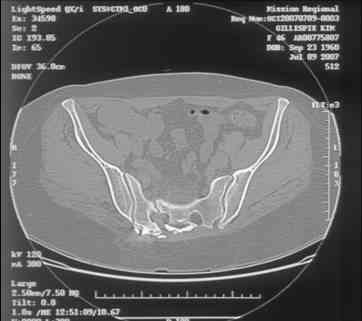

Re: Sacral Non-Union

Here is a magnified view. Sorry about the quality but the CT was scanned into our system.

dave